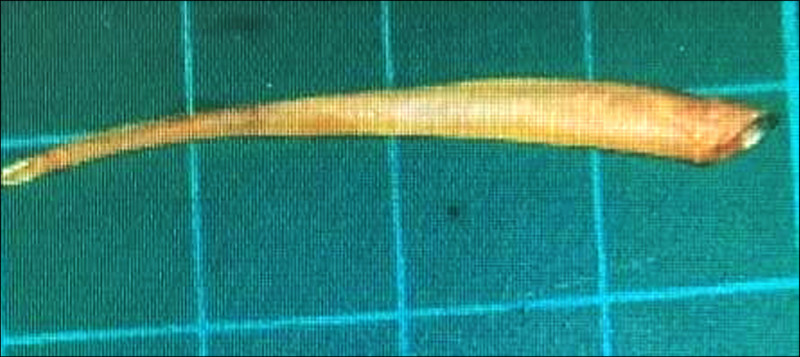

圖片來源/詩華日報,下同

根據《詩華日報》報導,當時男子已神智不清,院方初步研判是腹部感染,將其移送重症病房,並開始注射抗生素。然而,當醫生替男子開刀後,發現他的腸子裡有根約2公分長的魚刺,且還穿破小腸,出現約0.5公分的洞,導致腸道感染。

事後,男子切除約10公分的腸道,但他病況未好轉,到院8小時後因心臟驟停死亡。該案例紀錄在《國際外科手術案例報告》 (International Journal of Surgery Case Reports) 期刊,醫生指出,以上情況相當少見,異物通過消化道時,有時會卡在消化系統的狹窄處,但只有1%需要開刀。